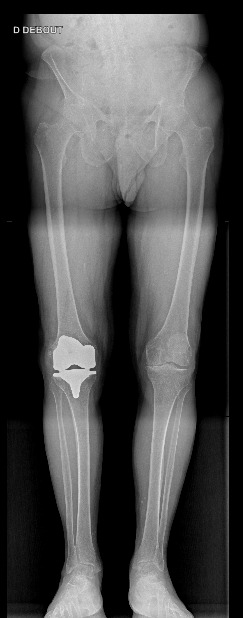

Description

La prothèse totale du genou est une intervention chirurgicale qui a pour but de remplacer les portions articulaires du genou détruites par l’arthrose ou d’autres maladies, par des composants artificiels en métal et en plastique conçus pour reproduire la forme des surfaces articulaires normales. Concrètement, la prothèse de genou comporte généralement trois pièces : une pièce fémorale qui recouvre l’extrémité inférieure du fémur, une pièce tibiale qui remplace le plateau supérieur du tibia, et parfois un implant patellaire (rotulien) fixée derrière la rotule pour reconstituer la face articulaire de celle-ci. L’ensemble de ces implants articulés entre eux redonne au genou une mobilité aussi complète que possible et une bonne stabilité. La prothèse de genou est indiquée essentiellement en cas d’arthrose du genou (gonarthrose) provoquant des douleurs importantes, des déformations et un handicap fonctionnel, lorsque les traitements conservateurs ne suffisent plus. Elle peut également être proposée après certaines fractures articulaires graves du genou ou en cas de polyarthrite évoluée touchant le genou.

Technique chirurgicale

La pose d’une prothèse totale de genou se déroule sous anesthésie (rachianesthésie loco-régionale ou anesthésie générale). Le chirurgien réalise une incision sur la face avant du genou, puis ouvre la capsule articulaire en passant généralement par le côté interne de la rotule pour exposer l’articulation du genou. Les surfaces articulaires usées sont alors préparées : le cartilage abîmé et une fine couche d’os sous-chondral sont retirés à l’extrémité du fémur et sur le plateau tibial à l’aide d’instruments de coupe spécialisés. Cela permet de sculpter l’os selon la forme adéquate pour recevoir les composants de la prothèse. La rotule est également régulièrement préparée : on peut réséquer sa surface articulaire pour y placer un implant patellaire (selon les cas). Une fois les calculs d’alignement effectués, les trois composants prothétiques (fémoral, tibial et éventuellement rotulien) sont fixés en place, souvent à l’aide de ciment chirurgical pour assurer leur stabilité immédiate. Le chirurgien vérifie ensuite la bonne mobilité et la stabilité du genou reconstruit en le pliant et le dépliant, avec la prothèse en place. Les tissus (tendons, muscles) et la peau sont ensuite suturés normalement. L’intervention dure en moyenne une heure et demie. À la fin de l’opération, un pansement stérile est appliqué et le genou peut être maintenu temporairement immobile par une attelle pour protéger les tissus dans les premières heures.

Prothèse sur mesure, chirurgie assistée par ordinateur, chirurgie assistée par robot

Au CHU d’Orléans, nous avons la chance de pouvoir proposer deux approches technologiques complémentaires pour la prothèse totale de genou (PTG) :

• Prothèses sur mesure / guides personnalisés : À partir d’un scanner, on conçoit des guides de coupe et des implants adaptés à l’anatomie du patient. Objectifs : meilleure correspondance taille-morphologie, respect des axes et gain potentiel de confort, avec une planification précise en amont.

• Chirurgie assistée par navigation et par robot : le robot aide à exécuter les coupes osseuses dans des limites définies par une planification 3D avant l’opération et qui est adaptée pendant l’opération. Bénéfices attendus : précision de positionnement, préservation osseuse et meilleur respect des tissus mous.